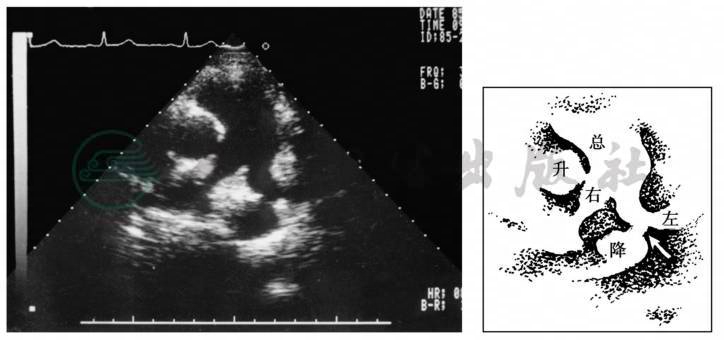

超声心动图是首选的诊断方法,可以显示未闭的动脉导管,并能测量长度、内径和分流量,可以显示各房、室扩大以及发现其他心血管畸形,可以估测肺动脉压力(图2)。

图2 超声显像所示动脉导管未闭情况

注:↑=动脉导管;总=肺总动脉;左=左肺动脉;右=右肺动脉;升=升主动脉;降=降主动脉。